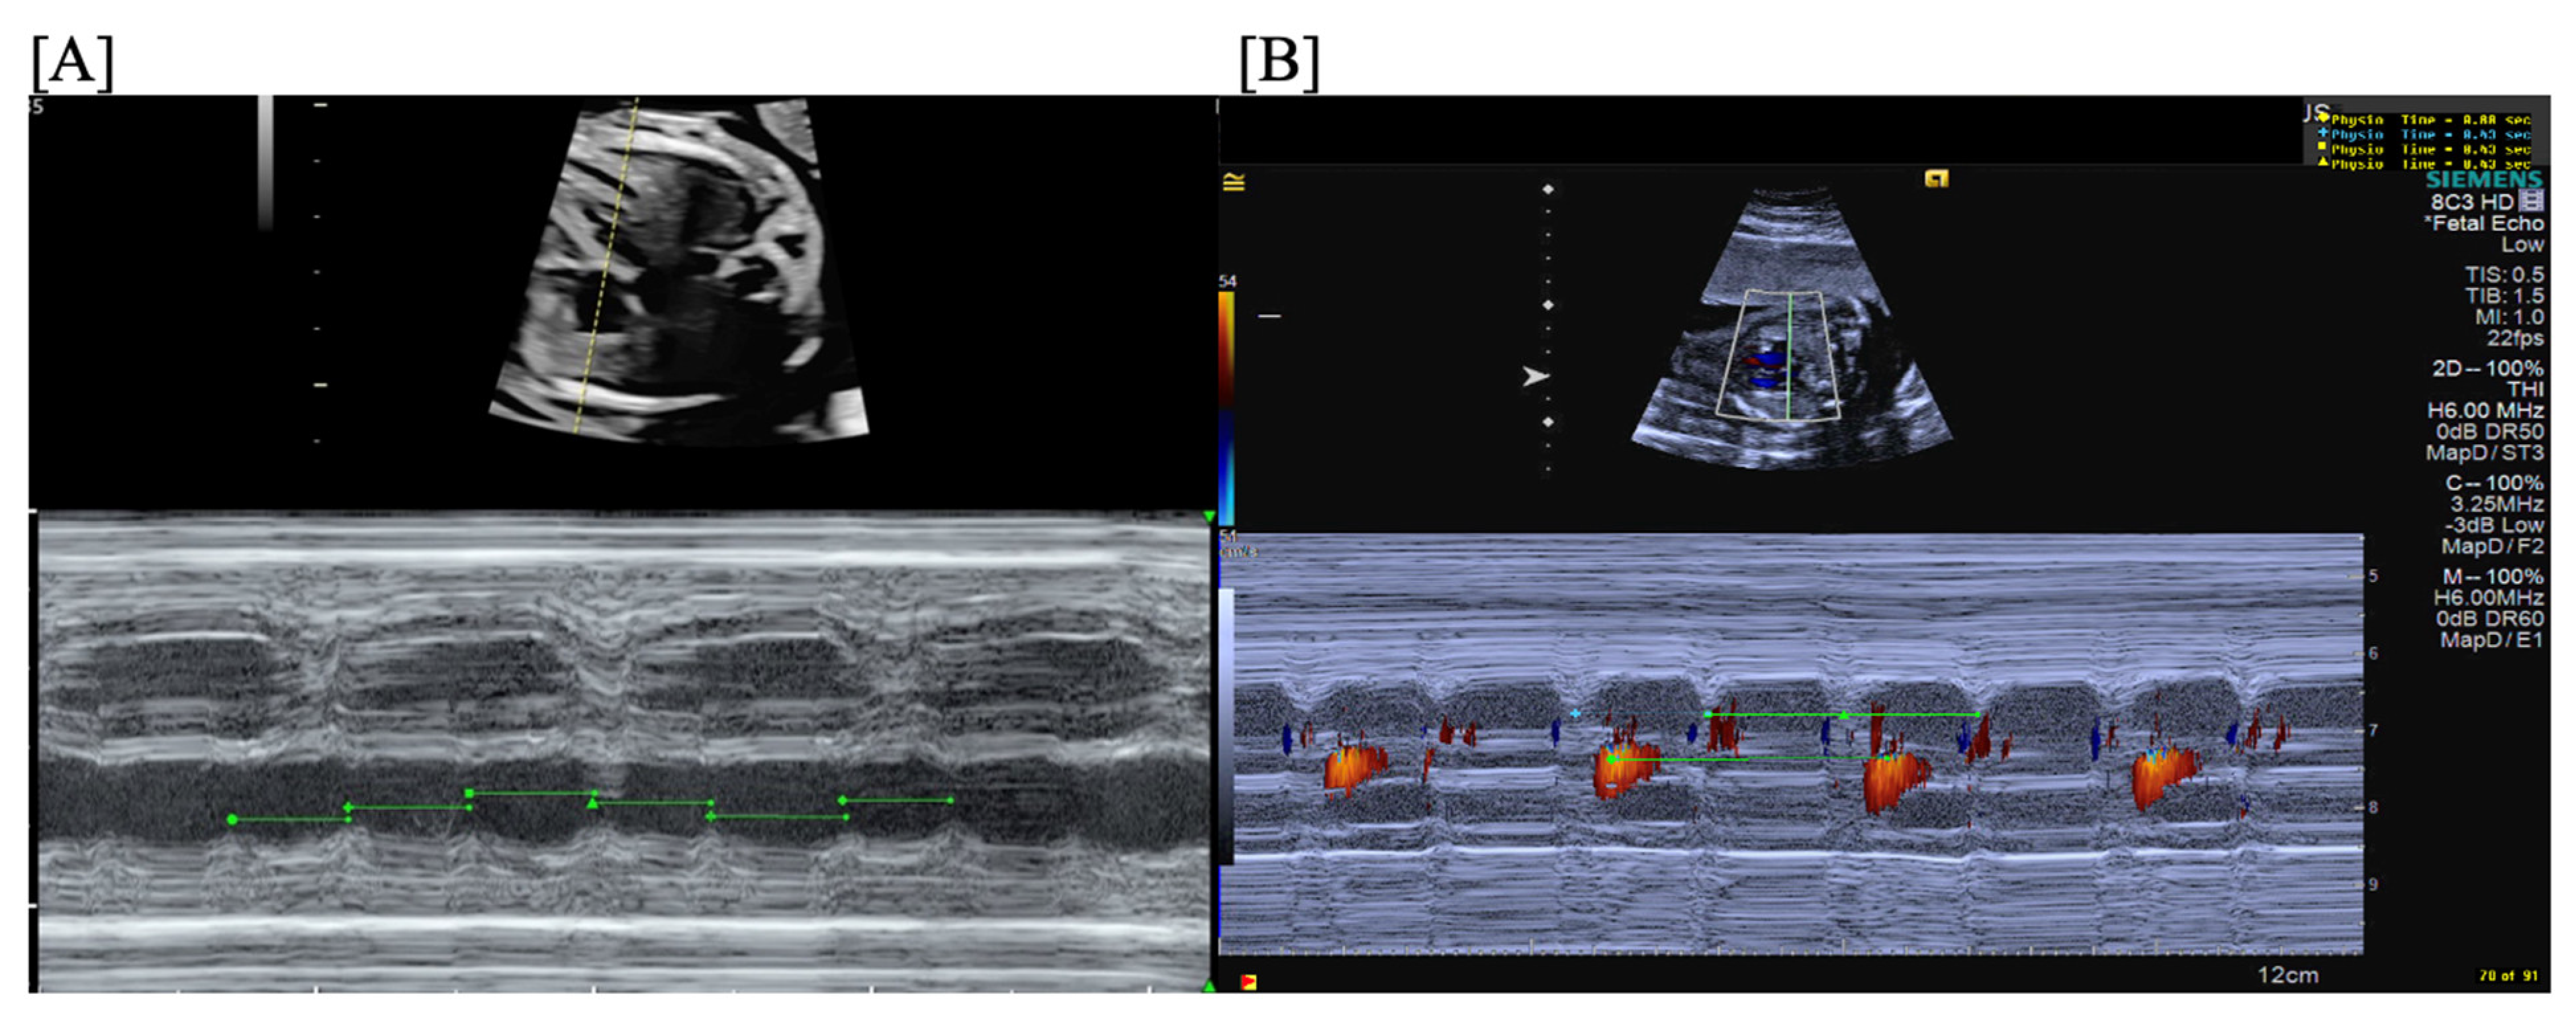

- Short VA SVT (Figure 3 and Figure 4) demonstrates a ventricular–atrial (VA) interval that is less than half of the ventricular–ventricular (VV) interval (VA:AV ratio < 1) and a sudden onset and termination of tachycardia; tachycardia usually terminates with a non-conducted atrial contraction. Short VA SVT includes AVRT (also known as orthodromic reciprocating tachycardia, ORT) and atrioventricular nodal reentrant tachycardia (AVNRT). Short VA SVT typically presents after 18 weeks of gestation.

- Long VA SVT (Figure 4) demonstrates a VA interval that is more than half of the VV interval (VA:AV ratio > 1). Long VA SVT includes EAT and PJRT. A distinguishing feature of EAT is tachycardia termination with ventricular contraction. Long VA SVT may occur as early as 12 weeks of gestation. Because long VA tachycardias have slower rates, they are less likely to cause hydrops.